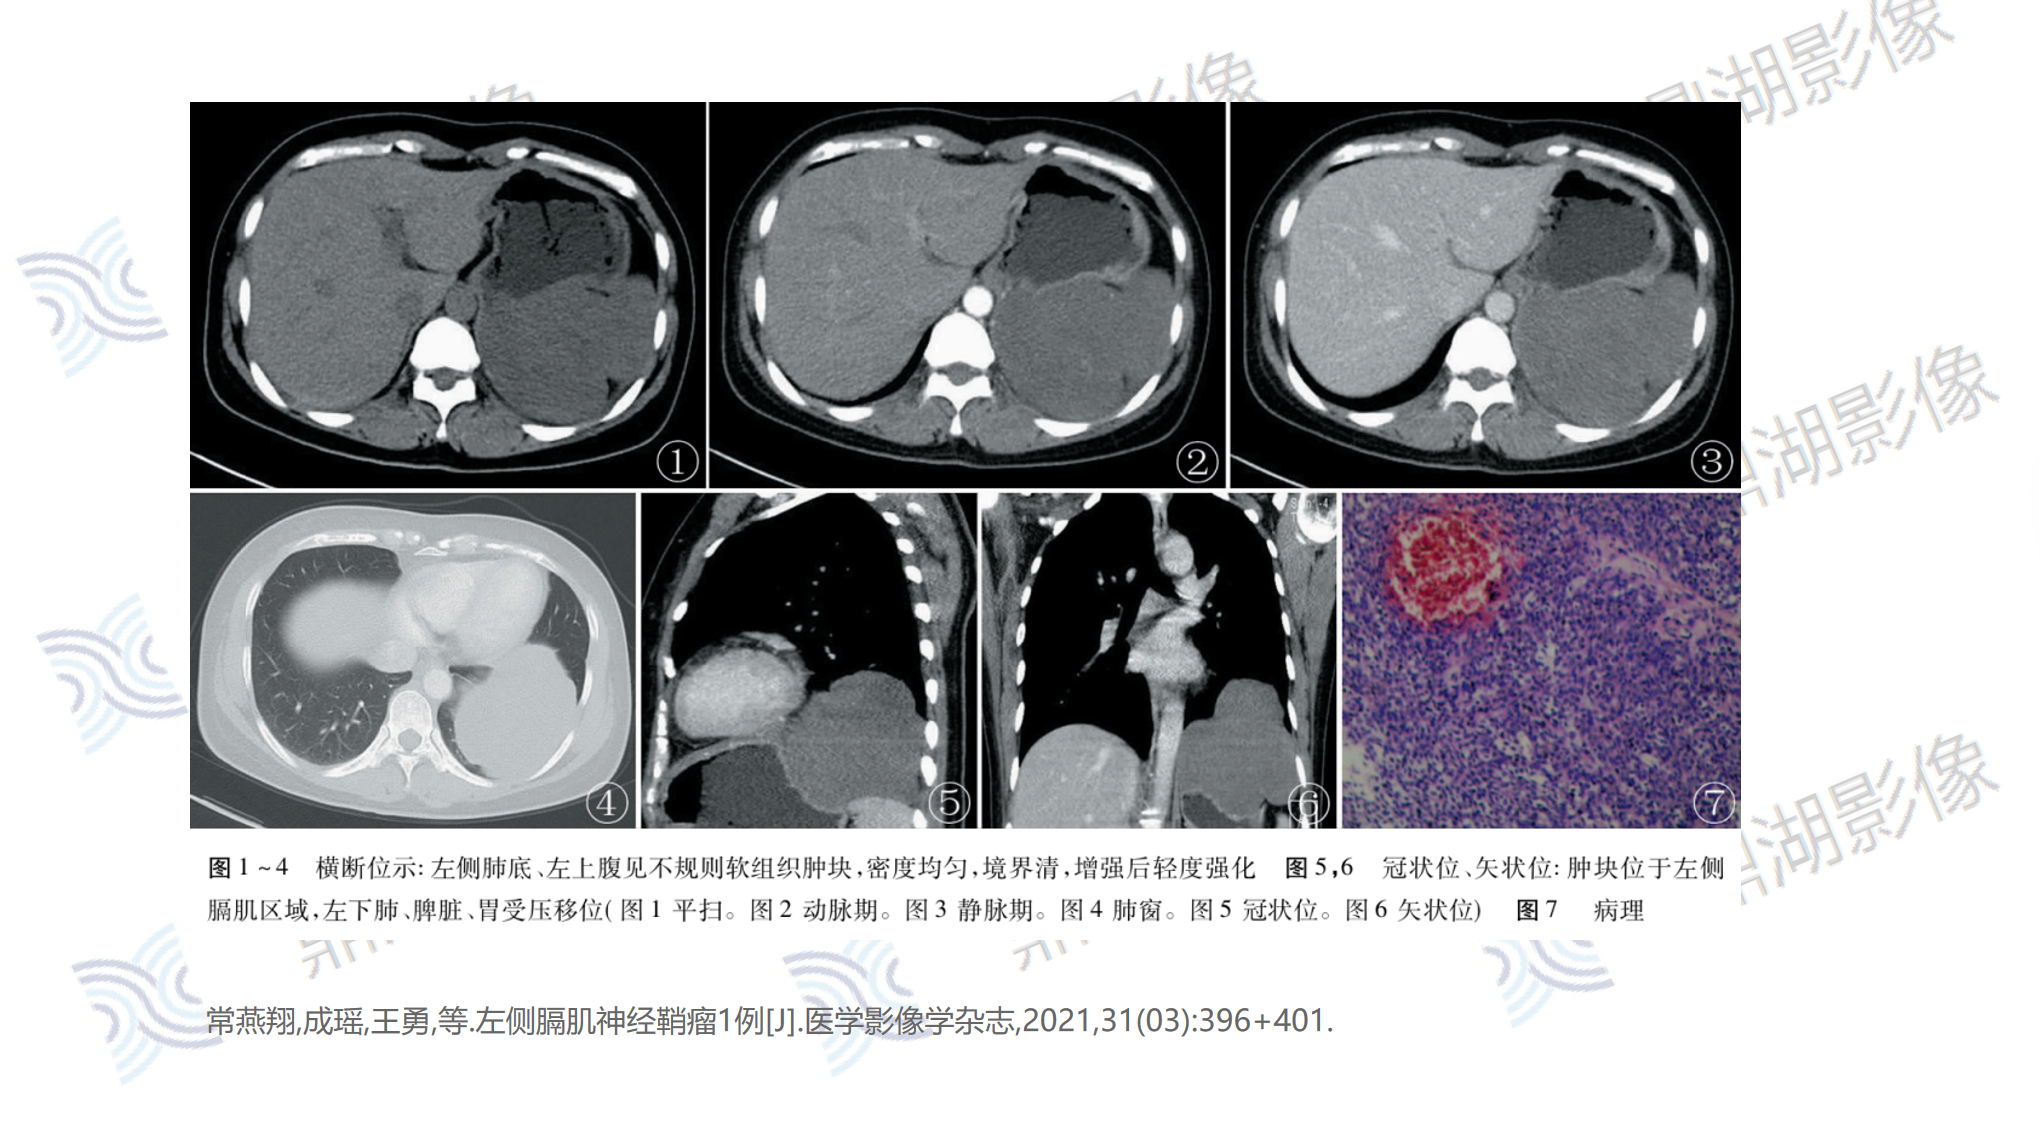

主诉:因腹痛就诊,CT示左侧横膈区占位